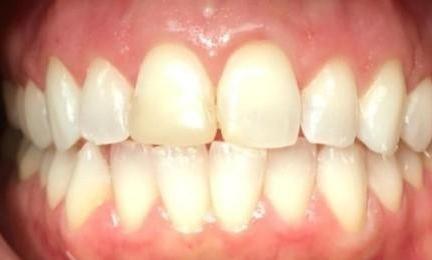

This case combined Invisalign, composite restorations, whitening and veneers to restore damage done from decades of grinding. Most dental offices would have placed crowns on all the back teeth, but with Invisalign treatment to set the bite, we were able to preserve more of the patients teeth while saving time and expense.